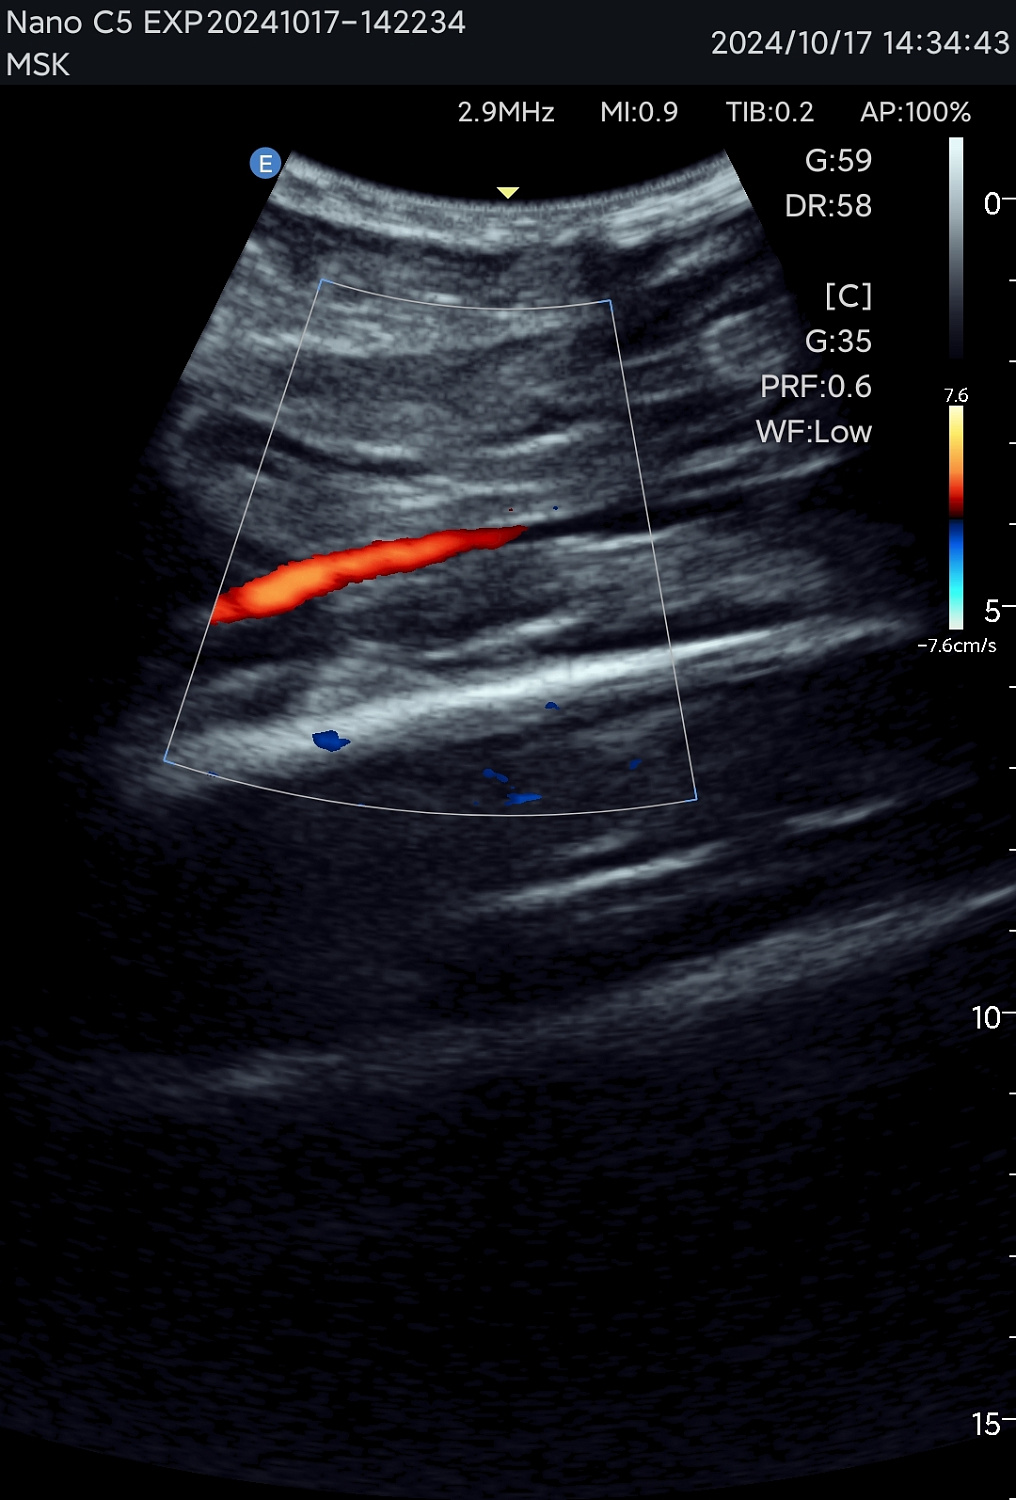

Технология зональной сонографии — это совершенно новый подход к получению и обработке ультразвуковых изображений. EDAN SynSight может использовать всю информацию, содержащуюся в наборе эхо-данных, полученных в каждой большой зоне, и таким образом охватывать поле зрения за меньшее количество циклов передачи/приёма. Исходная необработанная эхо-информация многократно обрабатывается в процессоре канальной области для формирования оптимальных изображений.

Новый стандарт портативного УЗИ

Используйте перспективную технологию визуализации в портативном УЗ-сканере. Интерфейс устройства интуитивно понятен, а применение современных режимов сканирования обеспечивает эффективную и точную диагностику в различных клинических ситуациях. Аппарат оптимален как для работы в клинике, так и для неотложной помощи, повышая качество обследования у постели больного.